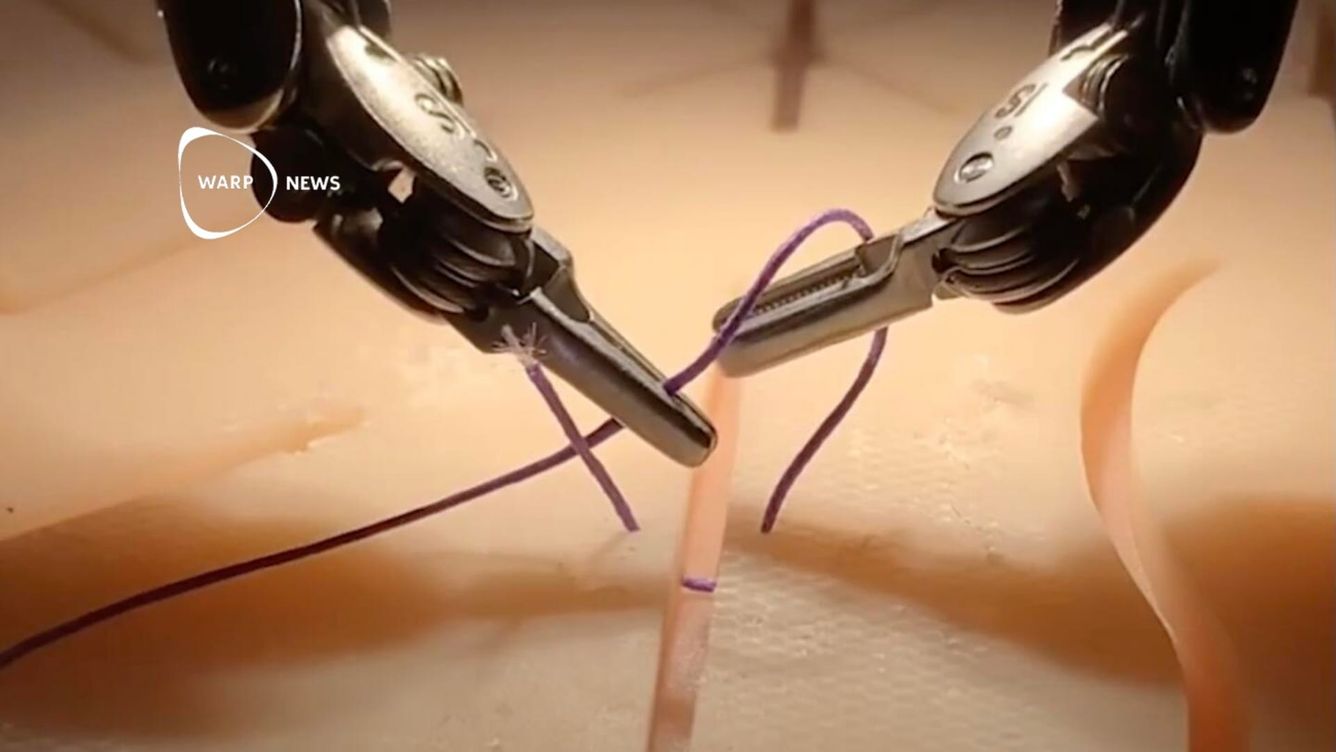

🦾 Robot lär sig kirurgi lika bra som kirurger genom att titta på video

En kirurgisk robot som tränats genom att observera videor av erfarna kirurger kunde utföra samma kirurgiska ingrepp med samma precision som mänskliga läkare.